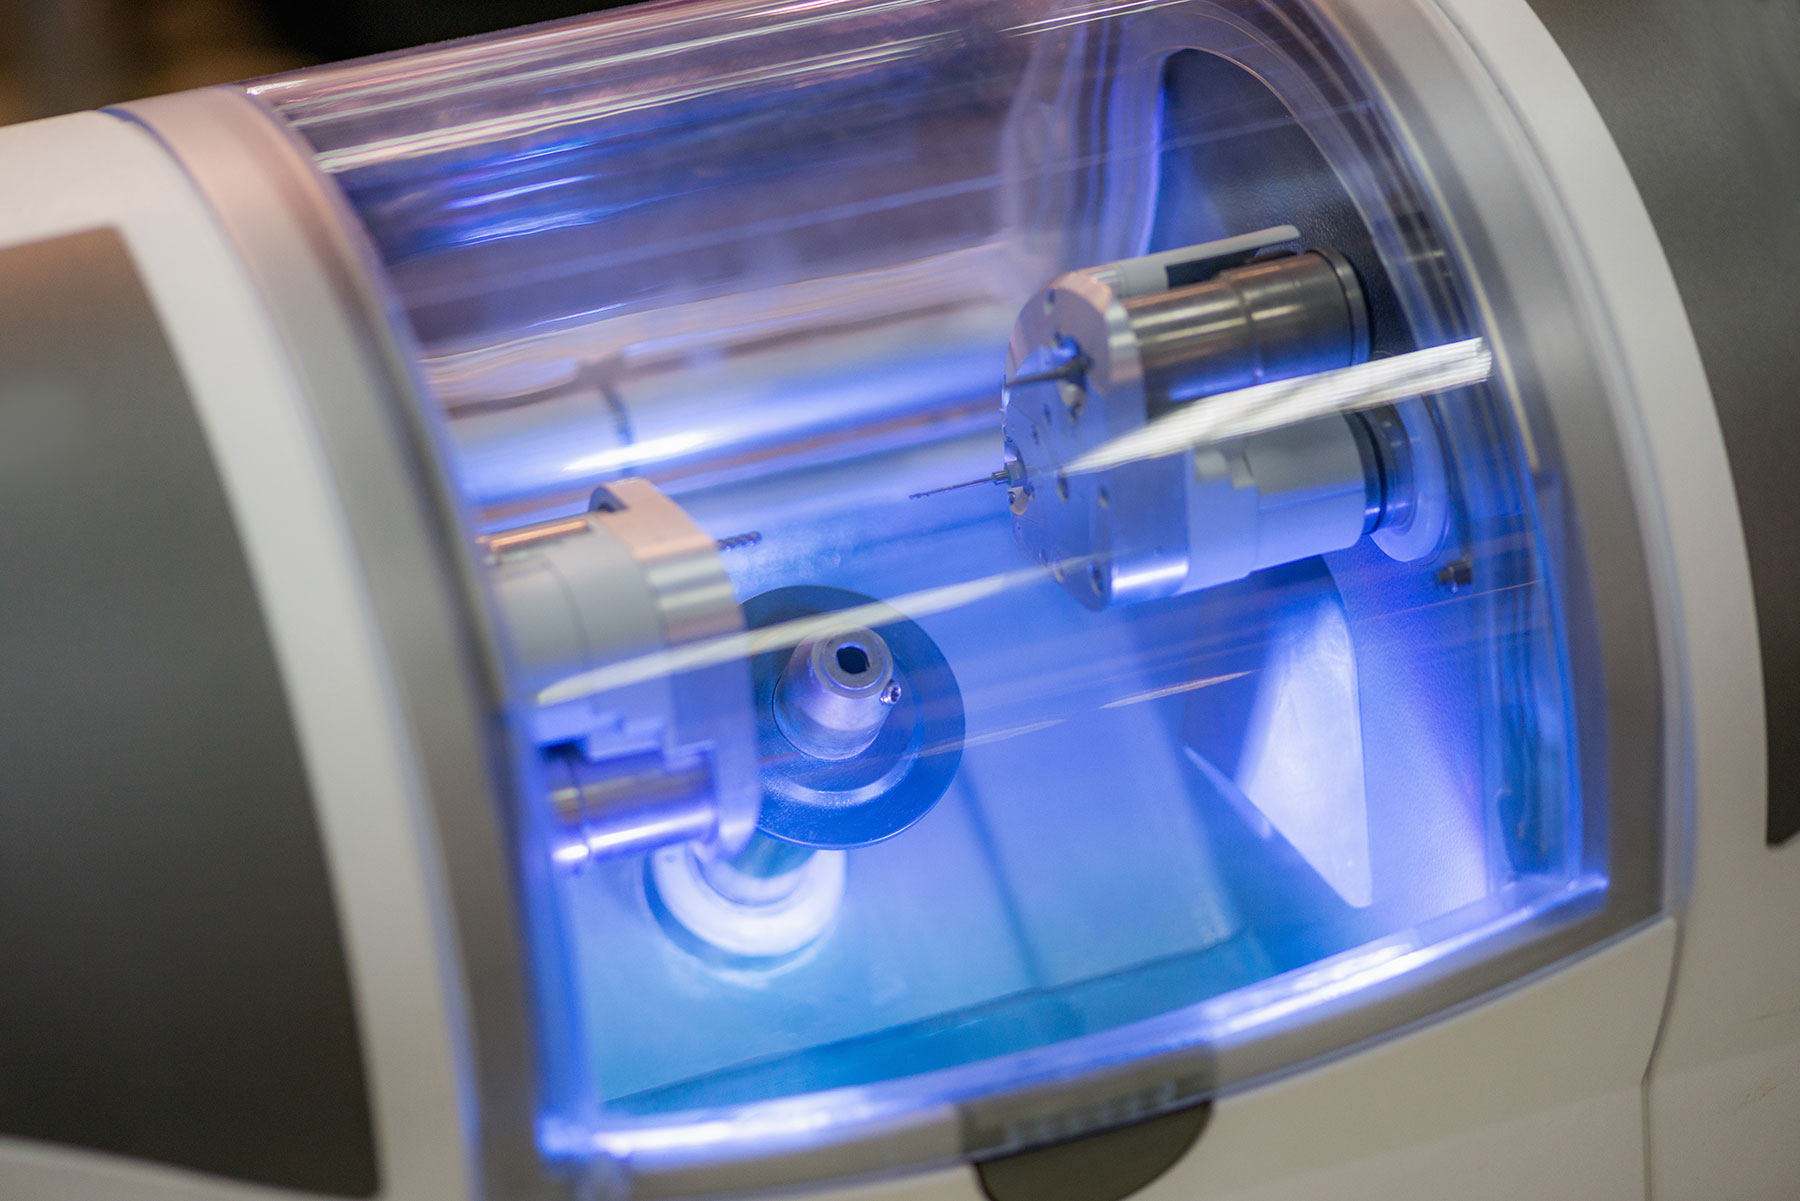

Intervenția de inserare a implanturilor dentare în os se face cu ajutorul anesteziei locale. Puteți opta și pentru anestezie generală, dar aceasta este indicata numai în cazuri medicale speciale. După instalarea anesteziei, se efectuează o incizie la nivelul gingiei pentru facilitarea accesului la nivel osos. Ulterior, se forează în os un lacaș cu ajutorul unor freze speciale care nu permit încălzirea osului în timpul intervenției. Fiziodispenserul NSK este un aparat de frezat în os care asigură un flux continuu de ser fiziologic răcit, putere reglabilă constantă indiferent de rezistența întâmpinată și controlul turațiilor.

Laborator de tehnică dentară digitală în cadrul clinicii, pentru realizarea lucrărilor protetice pe implant, într-o manieră rapidă și cu estetică și funcționalitate la nivel de excelență.

Realizăm la nivel de excelență toată gama de lucrări protetice pe implant dentar: coroană dentară pe implant pe suport zirconiu, punte însurubată pe implanturi dentare, supra-structuri pe implanturi dentare, conceptele All on 4, All on Six sau dinți ficși într-o zi, când cazul pacientului o permite.